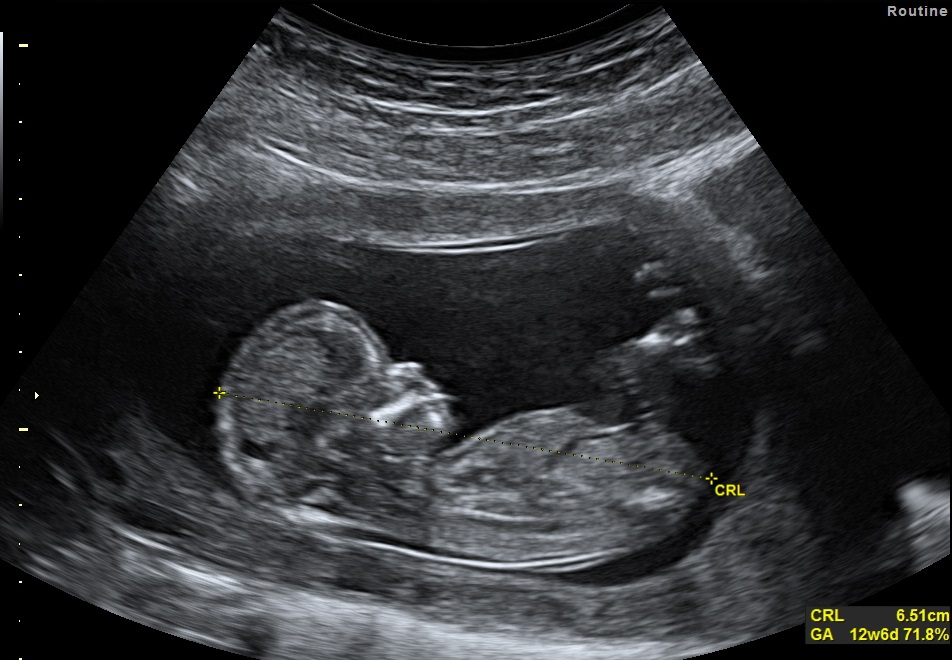

For early reassurance scans, we recommend waiting until at least 6 weeks into your pregnancy. It’s helpful to attend with a full bladder to improve image clarity. If we can’t get a clear view, we may offer a transvaginal ultrasound. Should the scan confirm that you’re too early for accurate results, we will gladly offer you a free rescan at a later date.